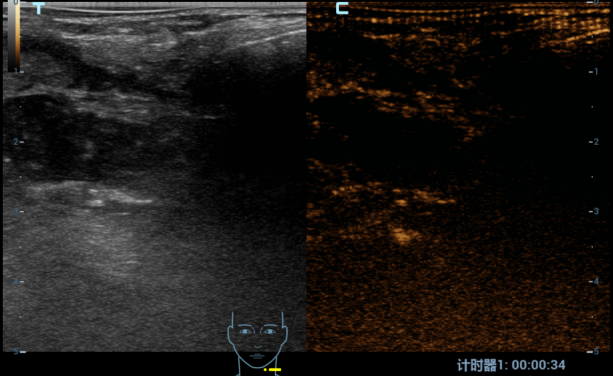

术后造影

结节无明显强化